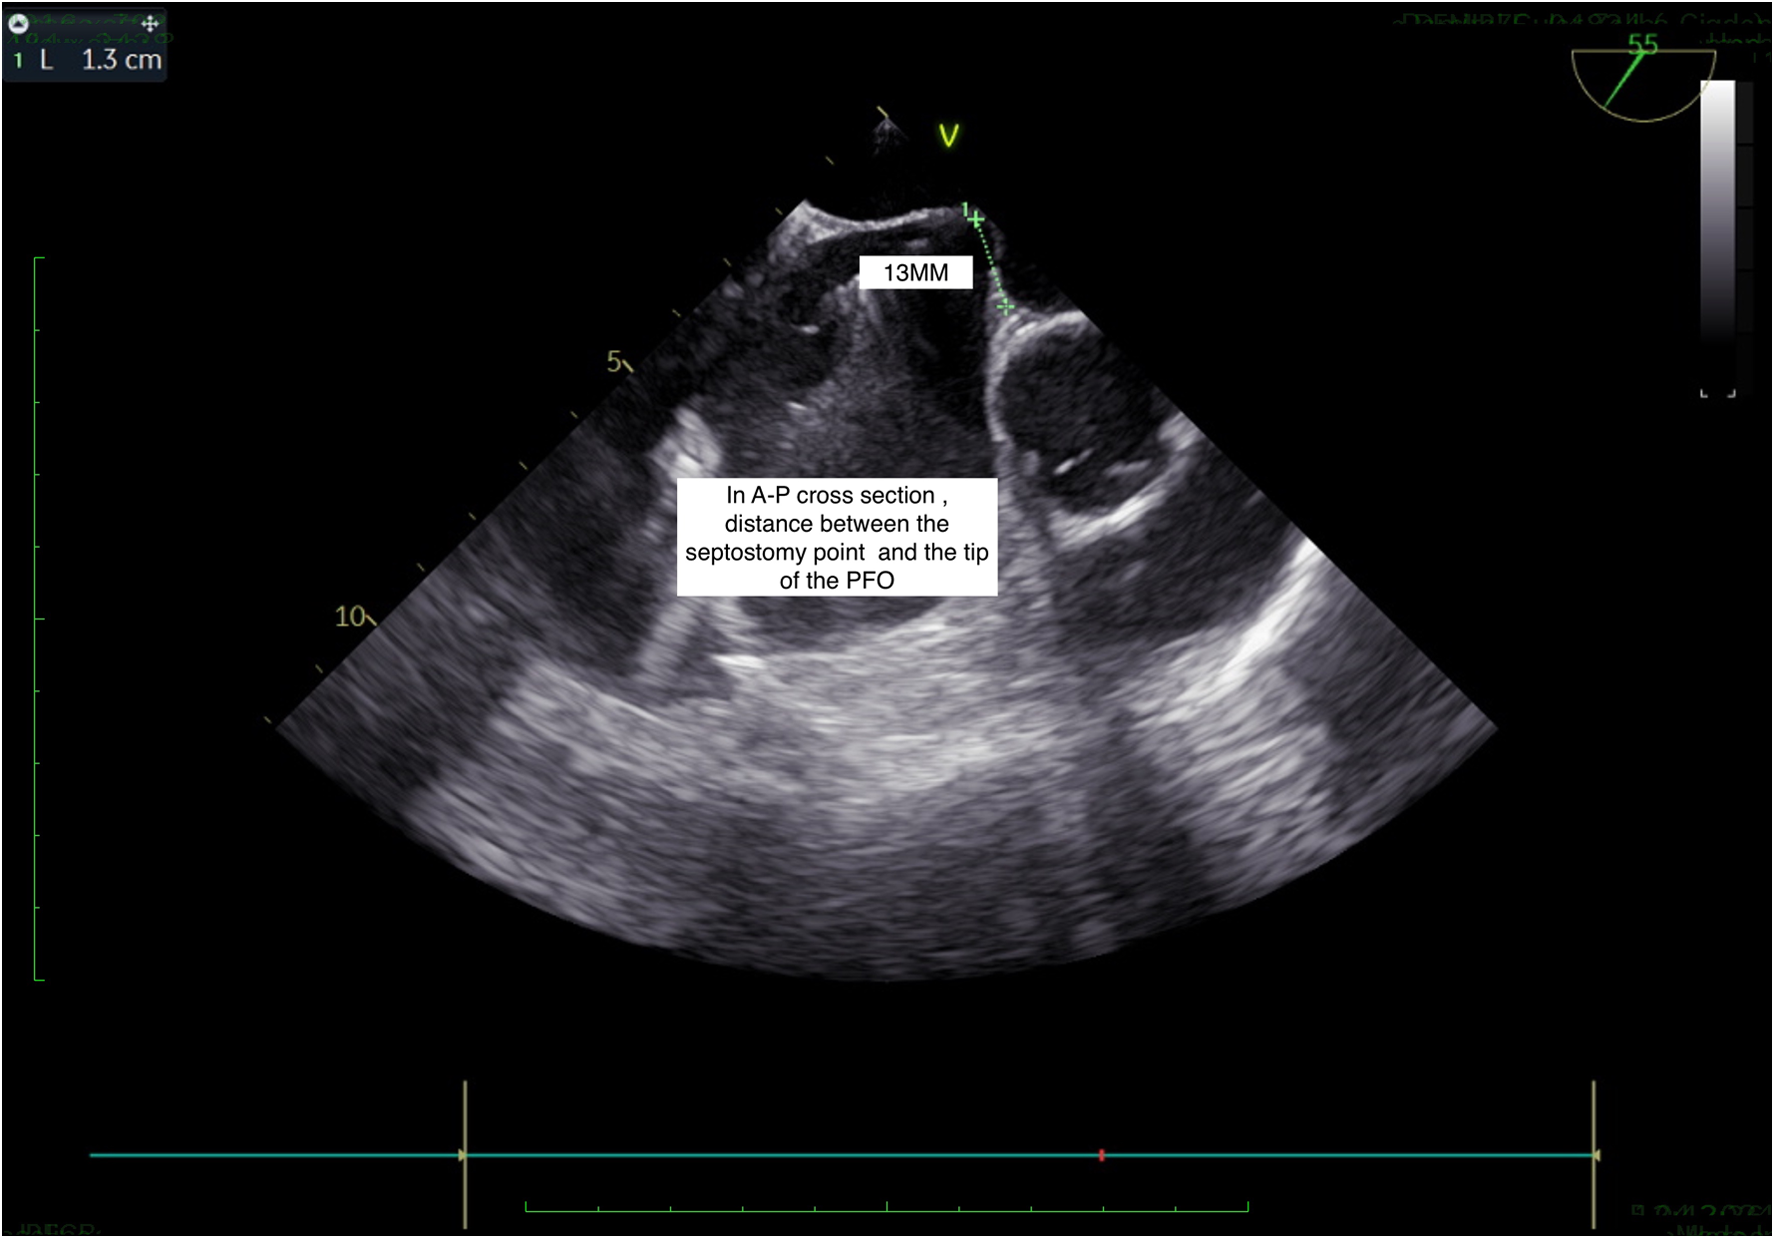

Figure 3

TEE, short axis view: septostomy distance.

If the septostomy point is determined by taking both A-P and bicaval sections, it provides a more accurate anatomical assessment, allowing for the correctly sized closure device to be selected. When the septostomy point was made inferiorly, the correct device size was selected without increasing the overall device size, ensuring proper closure and reducing the risk of a residual shunt (Figures 1A, 2–5). As shown in Figure 1B, in the A-P section, the distance between the septostomy point and the tip of the PFO is 8 mm, whereas in the bicaval section of the same patient, this distance is 13 mm (Figures 1C, 2–5). If the device had been selected by taking images from a single section (A-P), a small device would have been selected and a residual shunt would have been left.

(A) When the septostomy point was placed lower (9 mm), the correct device selection was made possible without increasing the device size. If the device had been selected by taking images from a single section (A-P), a too-small device would have been selected and a residual shunt would have been left. (B) In the anterior-posterior section, the distance between the septostomy point and the tip of the PFO is 8 mm. (C) In the bicaval section of the same patient, this distance is 13 mm.

If a septostomy is performed using images from only a single view (anterior-posterior or bicaval), the distance between the septostomy point and the tip of the PFO may not be accurately measured. This can lead to the selection of an incorrectly sized device, which might not fully close the PFO, resulting in a residual shunt. To avoid this issue, it is essential to use multiple views during imaging to ensure accurate measurement and appropriate device selection, which reduces the risk of residual shunts.